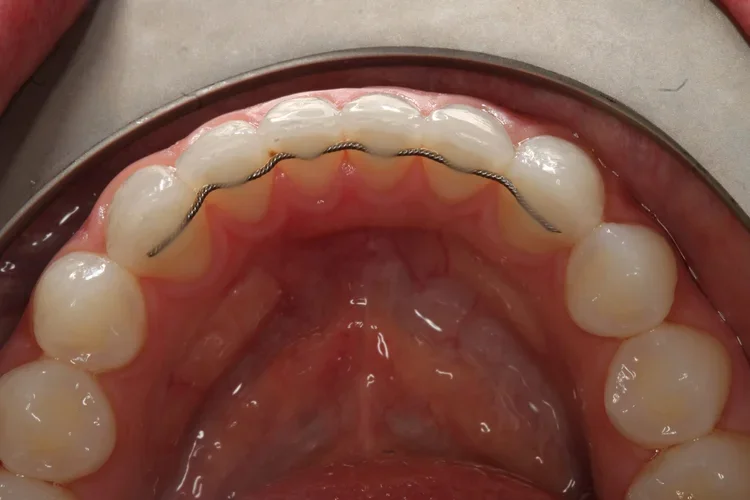

Fixed Retainers: What They Are, How Long They Last, and How to Care for Them (Worthing)

A fixed retainer (also called a bonded or permanent retainer) is a thin wire that is attached to the back of your front teeth after orthodontic treatment. Its job is simple: help stop teeth drifting back out of alignment over time.

An example of a fixed retainer before fitting

A fixed retainer is usually a smooth wire bonded behind the front teeth (commonly canine-to-canine). It is not visible when you smile and doesn’t need to be removed.

• Straight wire bonded to several teeth

• Braided wire (more flexible)

• Bonded to each tooth with small composite “pads”